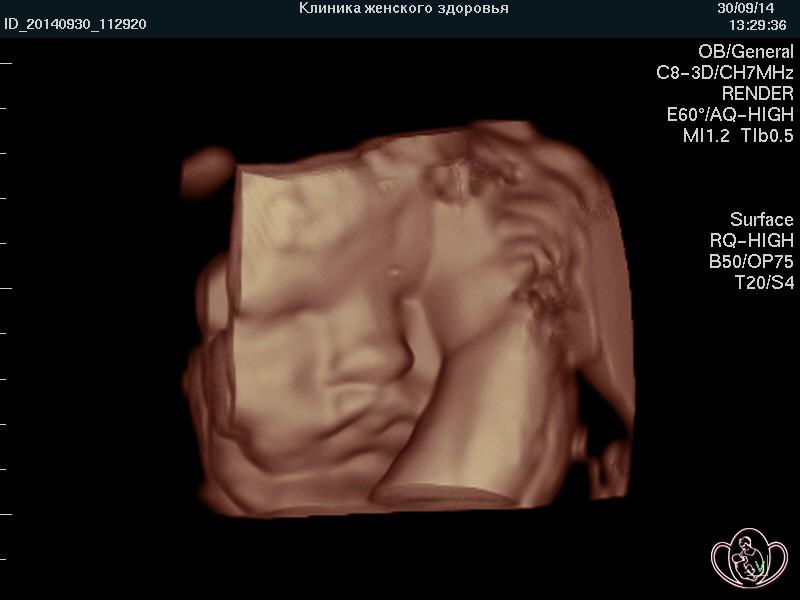

Чтобы определить сосудистую причину (фактор) бесплодия у женщин, в Спа-клинике женского здоровья проводится ультразвуковое исследование в 3D и энергетический допплер с использованием аппаратов экспертного класса.

| 3D фото овуляции: четко очерчены края свежего разрыва (овуляции) фолликула | ![]() |